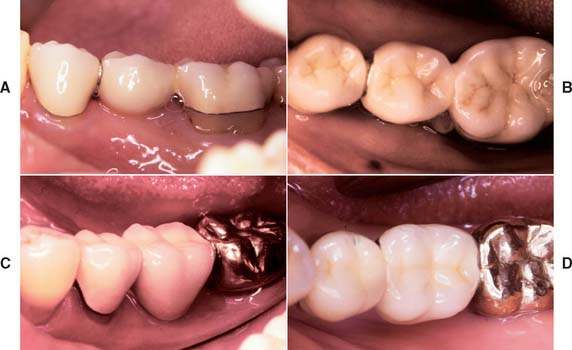

Unfortunately, periodontal disease often occurs after placement of fixed prostheses,26 especially where the cavosurface margin has been placed subgingivally27-29 or the prosthesis is overcontoured.30 Inflammation is more severe with poorly fitting restorations31 (Fig. 32-12), but even “perfect” margins have been associated with periodontitis.32 At recall appointments, particular attention is given to sulcular hemorrhage, furcation involvement, and calculus formation as early signs of periodontal disease. Improperly contoured restorations should be recontoured or replaced.

Fig. 32-12 Periodontal failure resulting from defective fixed prostheses. A, Inadequate margins and contour. B, Appearance before surgery. C, Flap reflected. D, Appearance after surgical recontouring. E, Radiograph of new cast restorations. F, Replacement restorations.